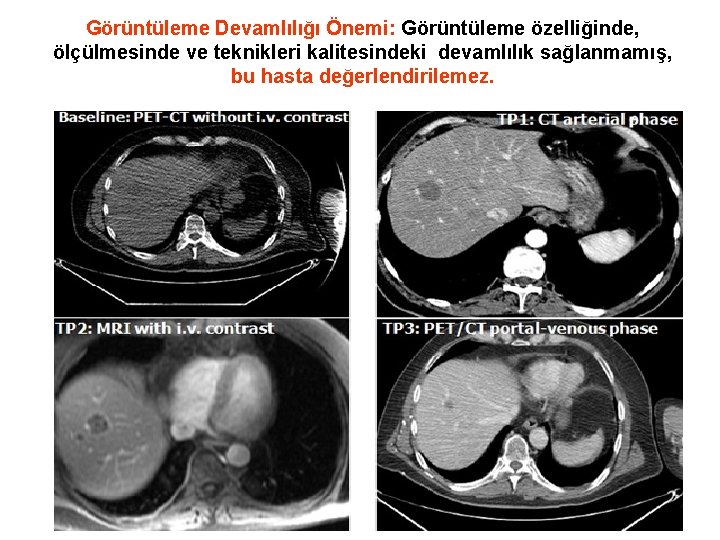

Görüntüleme Devamlılığı Önemi: Görüntüleme özelliğinde, ölçülmesinde ve teknikleri kalitesindeki devamlılık sağlanmamış, bu hasta değerlendirilemez.